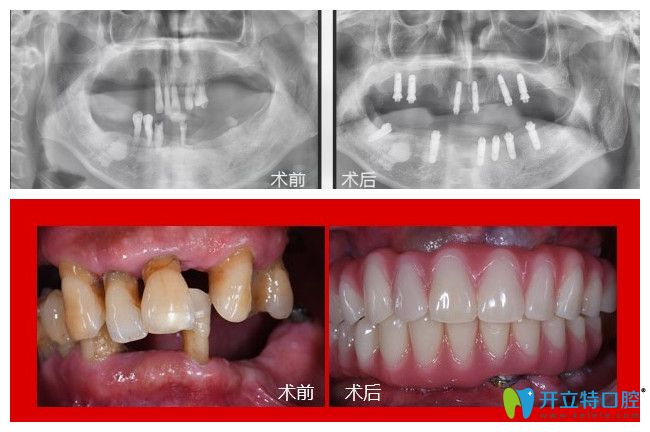

老爸今年60多歲,全口僅剩下三顆牙齒,在同事的介紹下我們從周口去鄭州德正口腔找劉杰彪院長給老爸做了全口牙齒種植,現(xiàn)在來給大家說說老爸做全口牙種植的經(jīng)歷和感受。